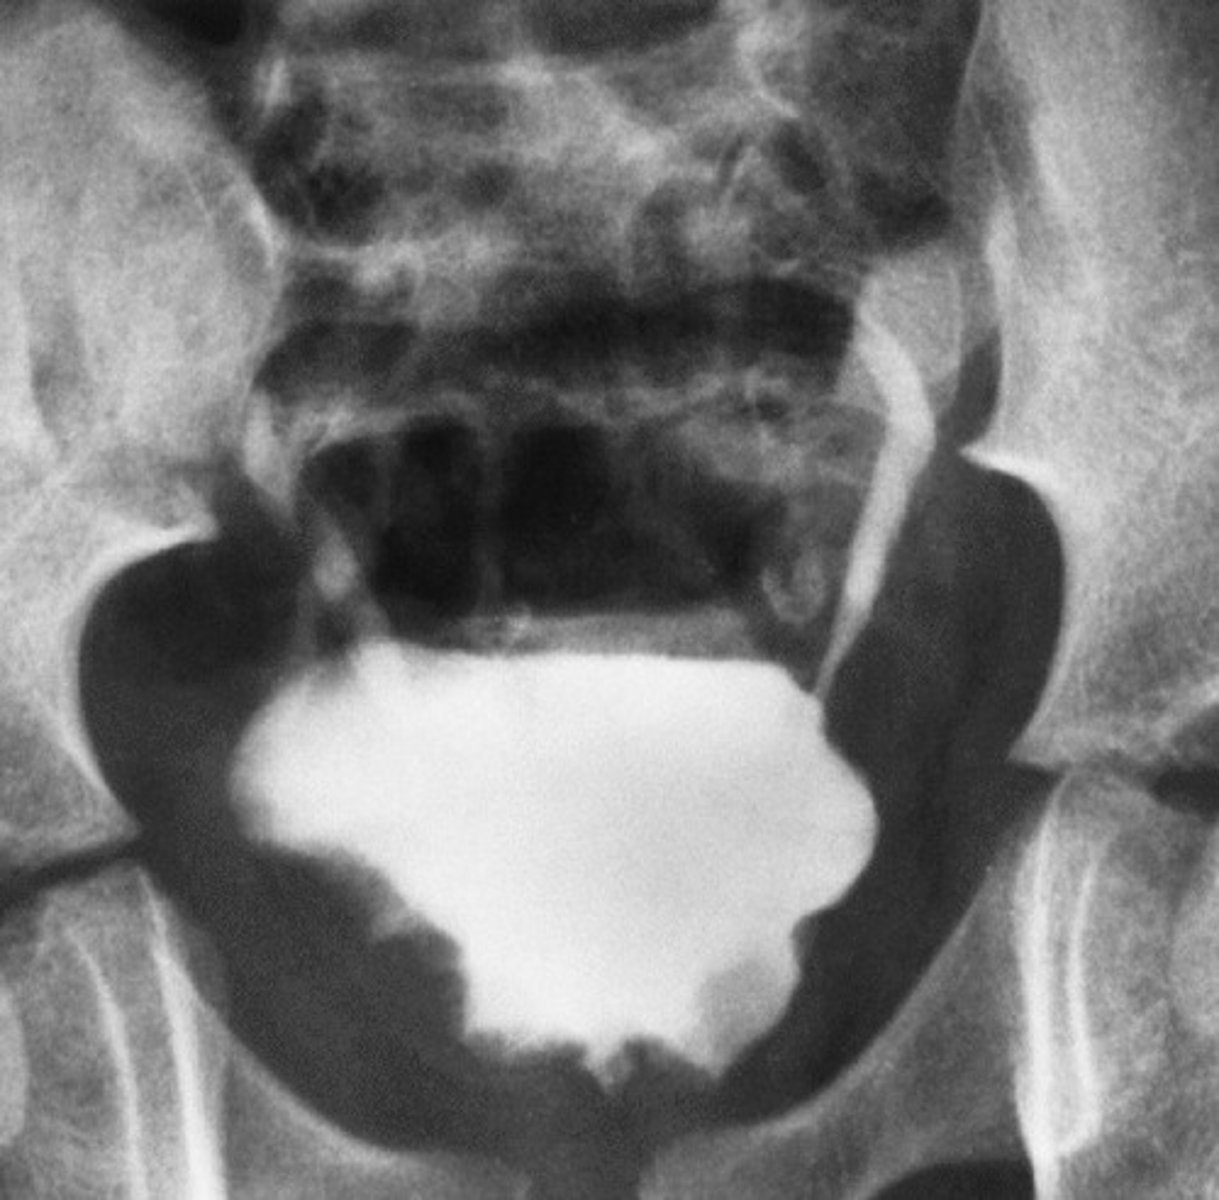

Bladder Stones

What occurs in men with obstruction and urinary tract infections (UTI) that varies in size and number?

Bladder Diverticula

What is this pathology?

Reflux